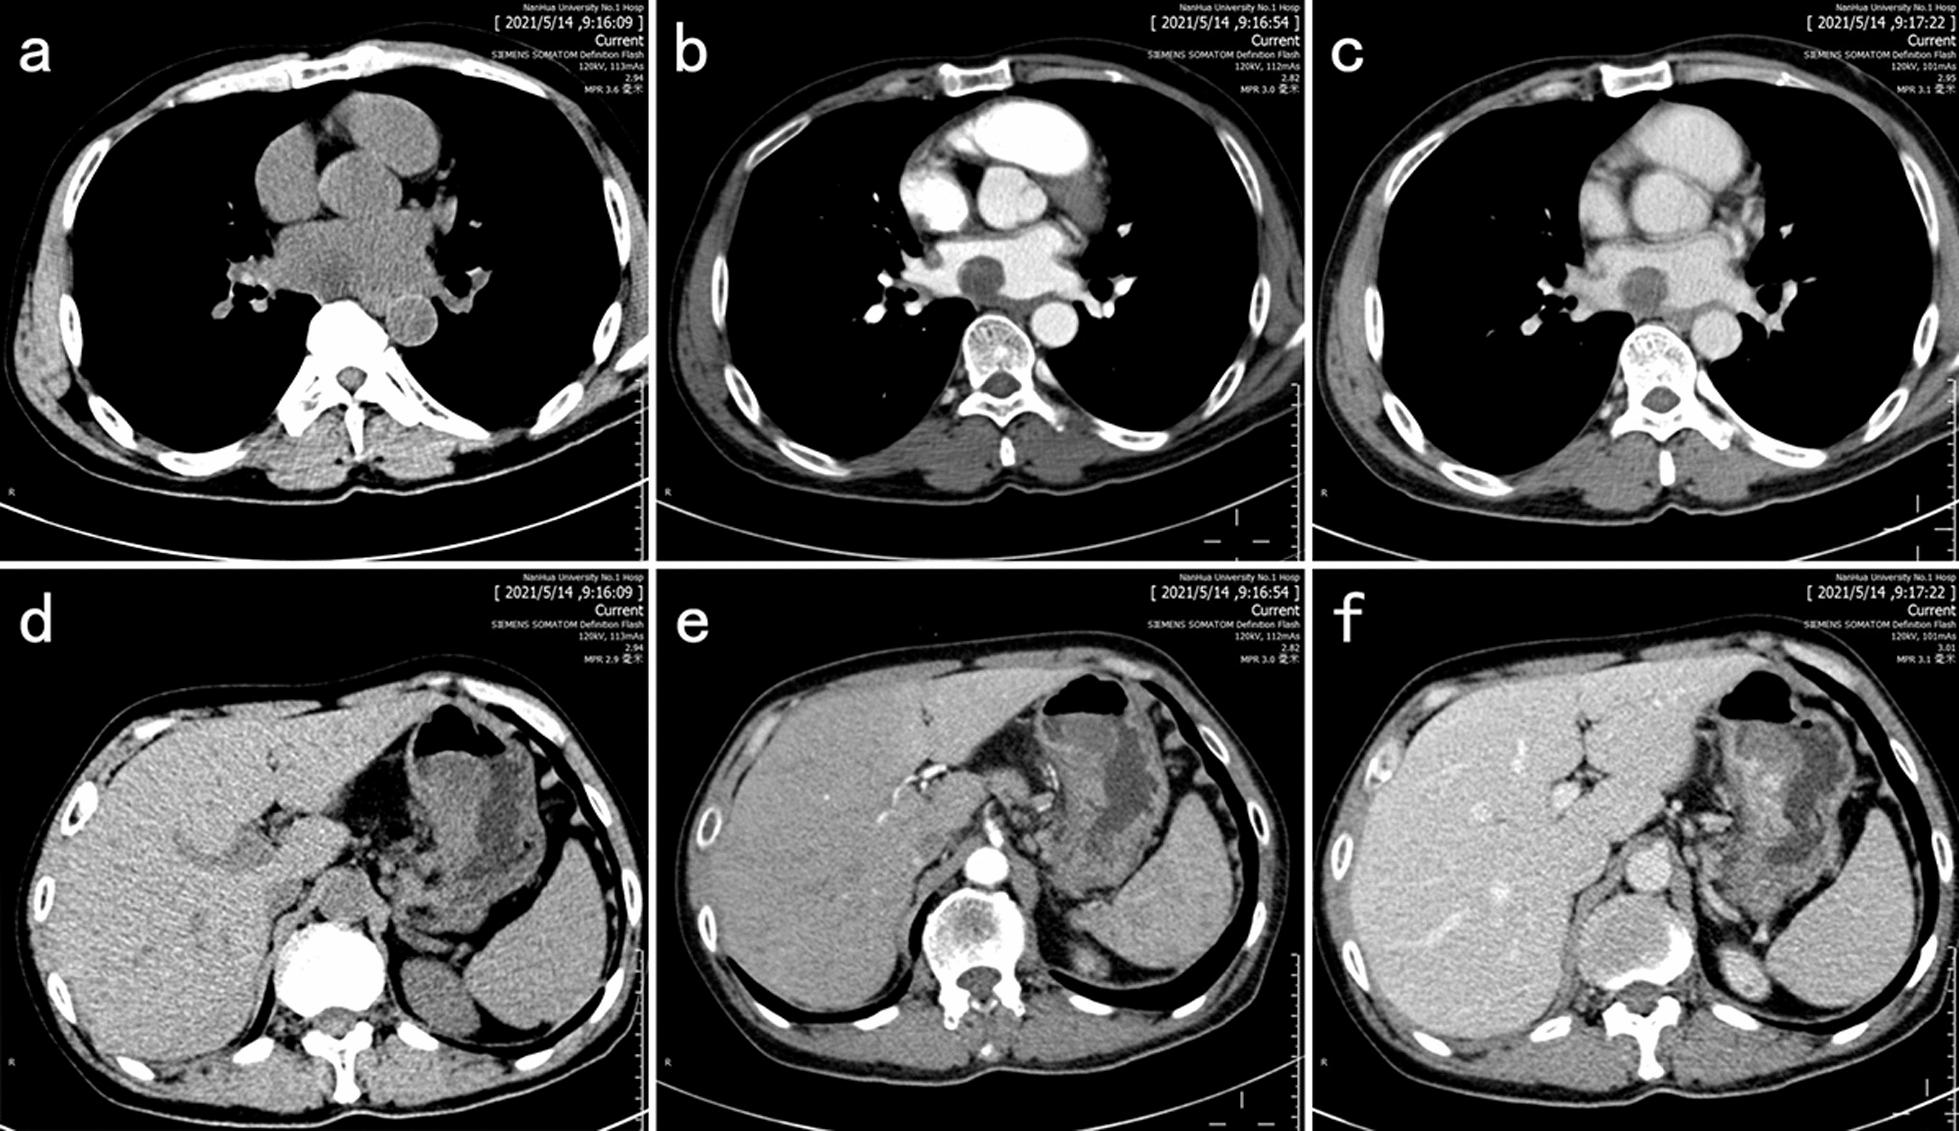

A 57-year-old male patient was admitted to the hospital with complaints of malaise, poor appetite, and epigastric pain with black stools. We found a mass in the patient's stomach and left atrium by contrast-enhanced computed tomography, 18 F-fluorodeoxyglucose positron emission tomography/computed tomography, and other tests. The patient underwent laparoscopic Billroth II subtotal gastrectomy and Braun's gastrointestinal reconstruction under general anesthesia. On the 46th day following stomach surgery, the cardiac tumor was removed under general anesthesia. The patient has treated with doxorubicin 70 mg of D1 chemotherapy two months after cardiac surgery. Postoperative pathological immunohistochemistry of the mass confirmed the diagnosis of an IMT. His review three months after the cardiac surgery suggested the progression of the left atrial mass, but he declined further treatment and finally died one month after the review.

一名 57 岁男性患者因乏力、食欲不振和上腹痛伴黑便入院。我们通过增强 CT、18F-氟脱氧葡萄糖正电子发射断层扫描/CT 等检查发现患者胃和左心房有肿块。患者在全身麻醉下行腹腔镜 Billroth II 式胃大部切除术和 Braun 胃肠重建术。在胃手术后第 46 天,患者在全身麻醉下行心脏肿瘤切除术。心脏手术后两个月,患者接受多柔比星 70mg D1 化疗。肿块的术后病理免疫组化结果确诊为 IMT。心脏手术后 3 个月复查提示左心房肿块进展,但患者拒绝进一步治疗,最终在复查后 1 个月死亡。